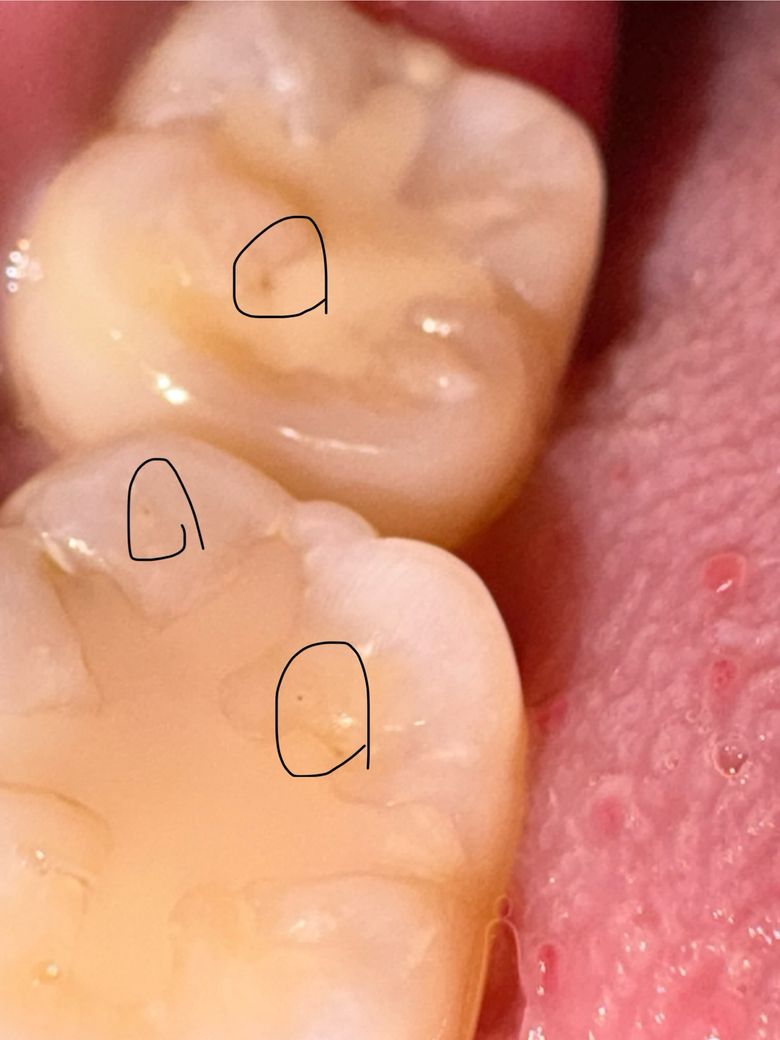

사진 내 표시한 부분이 충치인걸까요?

오른쪽 어금니 첫번째, 두번째 사진인데요

진료보기 전에도 사진처럼 검정부분이 존재했는데 선생님은 보시고도 충치가 없다고 하셔서 그냥 그런가보다 했는데 아파서 해당부분을 찍어서 사진으로 보니까 검정부분이 너무 잘 보여요

혹시 충치일까요? 아니면 홈이 파진부분이 빛의 각도 때문에 어둡게 보이는 걸까요?

사진으로 보이는 부분에는 충치가 있는 것으로 보이진 않습니다. 이전에 충전해놨던 재료의 구멍이 뚫린 것으로 보입니다. 크게 문제가 되진 않지만 걱정이 된다면 해당 부위를 치과용 재료로 충전할 수 있습니다.

충치로 보이지는 않습니다. 부분부분 틈새가 보이지는 않지만 당장 치료가 필요해보이진 않습니다.

사진에 보이는건 충치는 아니고 예전에 치료를 한곳이 틈이 생기면서 착색이 발생한거 같습니다.

엑스레이 찍어보는 것이 좋을 것 같습니다 하방 충치는 눈으로 안보일 수도 있고요 지금 사진상으론 변색일 수도 있고, 이차충치일 수도 있어보입니다